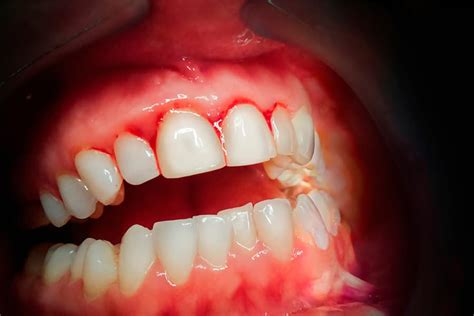

¿Es Normal el Sangrado Después de la Limpieza Dental?

Experimentar sensibilidad o molestias tras una profilaxis dental profesional es común. Si las encías presentaban signos de gingivitis, es probable que haya más sensibilidad post-tratamiento. Durante la limpieza, se eliminan los depósitos bacterianos y el sarro que causaban la inflamación, y el tejido necesita un periodo de recuperación.

Un ligero sangrado durante el cepillado en las primeras 48-72 horas es normal, especialmente si había inflamación gingival previa. Este sangrado debe disminuir progresivamente cada día. Si al tercer o cuarto día el sangrado no mejora o incluso aumenta, puede indicar que la técnica de cepillado es demasiado agresiva o que existe una condición periodontal que requiere seguimiento.